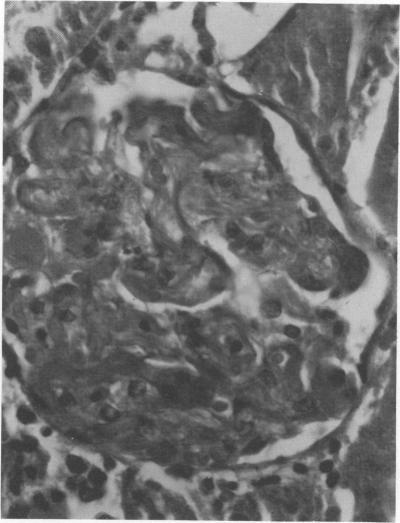

Endotoxic lipopolysachharide (LPS) was obtained from phenol-water extraction of cell walls prepared from mass-cultivated Fusobacterium necrophorum. The LPS was relatively free of nucleic acids and low in protein, and constituted about 4% of the cell walls. Upon acid hydrolysis, some of the components detected were hexosamines (7.0%), neutral and reducing sugars (50.5%), heptose (6.4%), 2-keto-3-deoxyoctonate (0.8%), lipid A (21.0%), and phosphorus (1.7%). Under electron microscopy the LPS appeared mainly as ribbon-like trilaminar structures, and upon chemical treatment it displayed a behavior resembling that reported in certain enterobacterial LPS. The LPS was lethal to mice, 11-day-old chicken embryos, and rabbits. Endotoxicity in mice was enhanced at least 1,380-fold by the addition of 12.5 mug of actinomycin D. Induced tolerance to lethal effect of the endotoxin and rapidly acquired resistance to infection by F. necrophrum viable cells were also demonstrated in mice. The endotoxin produced both localized and generalized Shwartzman reactions as well as biphasic pyrogenic responses in rabbits. These results firmly establish the presence of a classical endotoxin in F. necrophorum, thus providing strong support to our recent suggestion that cell wall-associated components may contribute significantly to the pathogenicity of F. necrophorum.

内毒素脂多糖(LPS)是从大规模培养的坏死梭杆菌制备的细胞壁经酚水提取获得的。该LPS相对不含核酸且蛋白质含量低,约占细胞壁的4%。经酸水解后,检测到的一些成分包括己糖胺(7.0%)、中性和还原性糖(50.5%)、庚糖(6.4%)、2-酮-3-脱氧辛酸(0.8%)、脂质A(21.0%)和磷(1.7%)。在电子显微镜下,LPS主要呈现为带状三层结构,经化学处理后,其表现出类似于某些肠道细菌LPS的行为。该LPS对小鼠、11日龄鸡胚和兔子具有致死性。通过添加12.5μg放线菌素D,小鼠的内毒素毒性增强了至少1380倍。在小鼠中还证实了对内毒素致死作用的诱导耐受性以及对坏死梭杆菌活细胞感染的快速获得性抗性。该内毒素在兔子中产生了局部和全身性施瓦茨曼反应以及双相热原反应。这些结果确凿地证实了坏死梭杆菌中存在经典内毒素,从而为我们最近提出的细胞壁相关成分可能对坏死梭杆菌的致病性有显著贡献的观点提供了有力支持。